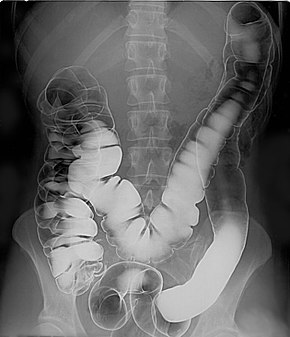

Itraconazole teblets 200 mg review in hindi/ uses, benefits,sideeffects daad khaj ki teblets elergy ko kam karne ki teblets. The picolax is not too bad to take but you must stay near a toilet all day. Fluka 150mg tablet full review in hindi uses of fluka tablet fluka 150mg tablet is used in the treatment of fungal infections.